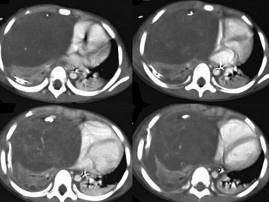

问题 14岁,男,胸闷咳嗽1个月,曾咳出过毛发,CT检查如图,请选择最可能的诊断 ( )

选项 A.纵隔血肿 B.胸内甲状腺肿 C.胸腺囊肿 D.畸胎瘤 E.食管囊肿

答案 D